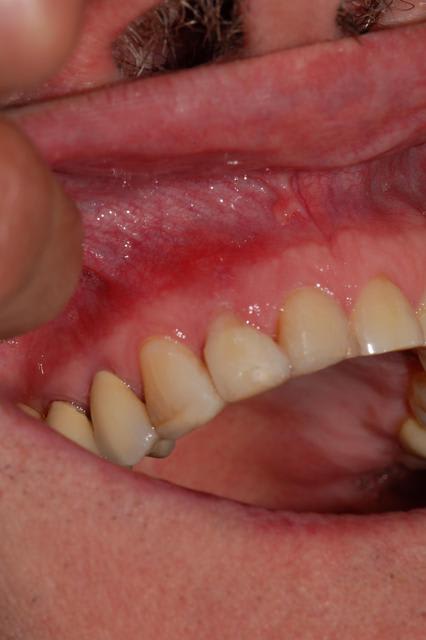

cas d'un patient arrivé vendredi en urgence, volumineux abcès vestibulaire sans fistulisation, au sondage poche de 8 mm en proximal: mésiale et distale, gencive attachée en vestibulaire,mobilité 3 pas le temps de prendre des photos, mais simplement une radio.

Traitement: assainissement par débridement des poches et de l'abcès à la povidone iodée diluée, puis au calbénium dilué, aéropolissage de la zone au bicarbonate puis injection dans les poches et dans la fistule crée au laser diode fibre 300µ, d'eau oxygénée à 10 volumes, attente 5 minutes puis activation au laser diode fibre 400µ et enfin biostimulation au laser diode fibre défocalisante pendant 1 mn. J'ai solidarisé 12 à 11 et 13, au composite flow.

j'ai oublié de vous dire que la dent n'est plus du tout mobile et que la gencive n'a plus d'aspect inflammatoire.